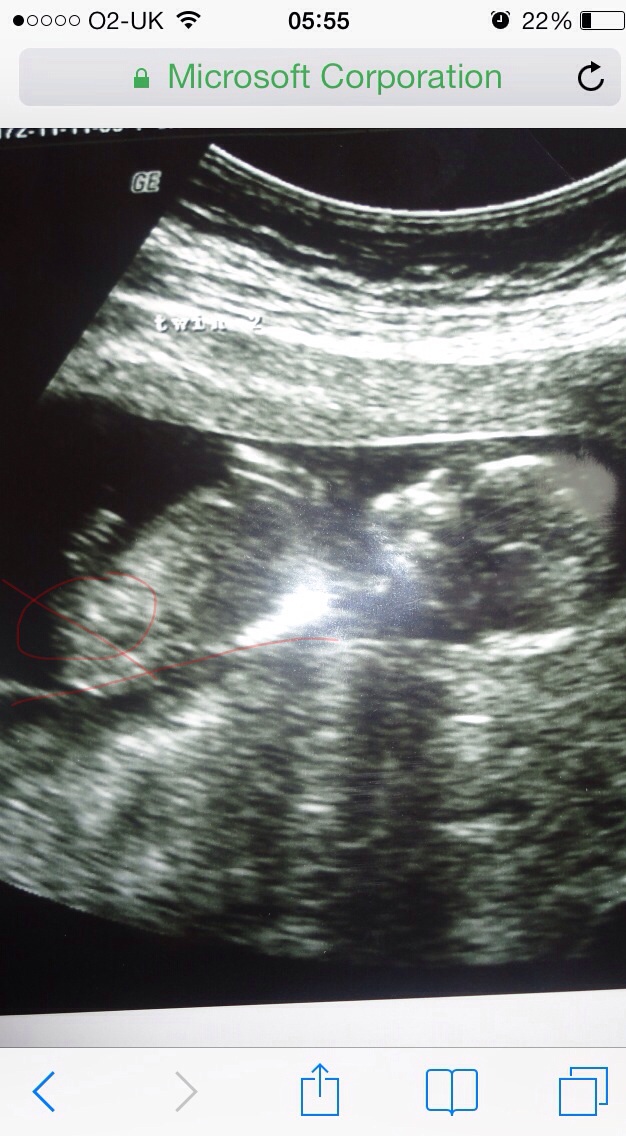

Attachment 26576

This is a pic of one of my twin boys. I prob got it wrong n circled the wrong thing! At the time I didn't really look! Xxxxxxxx

There is a wee angle but looks pretty flat. I would say girly but the length and slight shadow underneath has me swithering.

Tbh I still think at first glance it's girly but because the baby's bum is in the air at an angle it's harder to tell. Gl and keep us posted!

girl lean

Were you exactly 12 weeks? The closer to 13 weeks you are the more confident I am that this is a girly :-)

Leaning girl also due to lack of anything obviously blue :)

Possibly girl 75/25